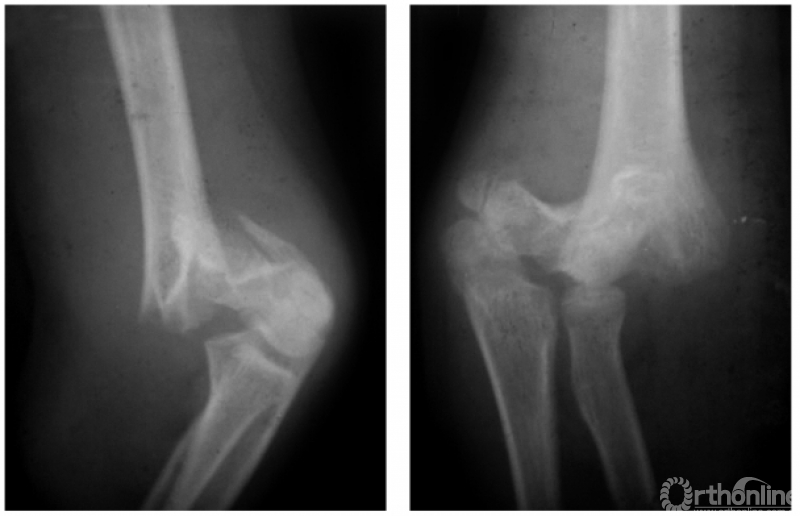

例3:伸展型兼尺偏并上尺桡关节脱位,即远折端向后、向内移位并上尺桡关节分开(图4)。

图4

例4:伸展型兼桡偏并肱骨内上髁Ⅱ度折,即远折端向后、向外移位,并内上髁骨块移至尺肱关节水平(图5)。

图5